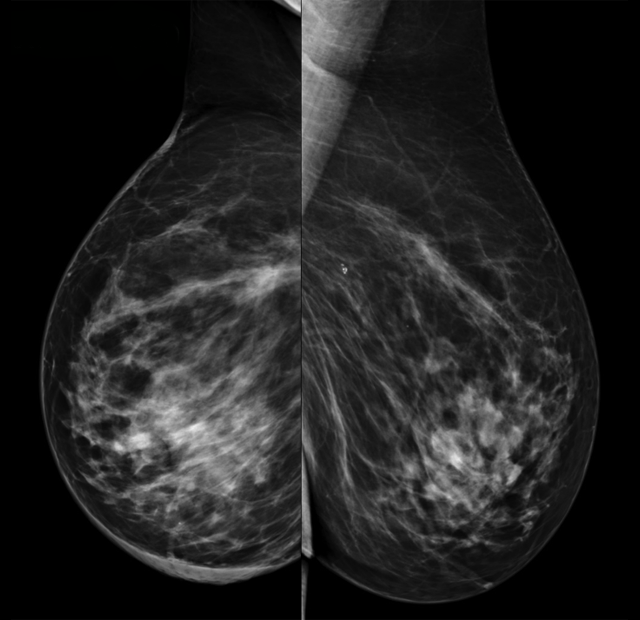

1. ¿Cuál sería tu informe radiológico de la mamografía y ecografía y qué recomendarías?

- A. Estudio dentro de la normalidad (BI RADS 1). Controles habituales.

- B. Cambios morfológicos en MD en relación con sus antecedentes, estable con respecto a control previo (BI RADS 2). Control anual.

- C. Cambios morfológicos en MD en relación con sus antecedentes, con engrosamiento cutáneo en cuadrantes inferiores (CCII) de MD (BI RADS 3). Control mamográfico y ecográfico en 6 meses.

- D. Cambios morfológicos en MD en relación con sus antecedentes, con engrosamiento cutáneo en CCII de MD de nueva aparición (BI RADS 4). Se recomienda biopsia cutánea (punch).

- E. Distorsión espiculada con microcalcificaciones en plano posterior de cuadrantes superiores (CCSS) de MD sospechosa de malignidad (BI RADS 5). Se recomienda biopsia con aguja gruesa (BAG).